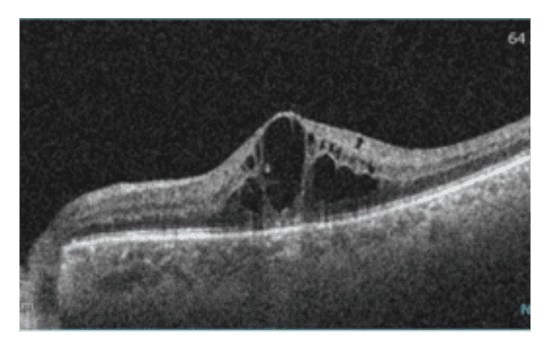

Upon examination, significant central edema and central retinal vein occlusion (CRVO) was observed in his left eye via fundus imaging and OCT. Despite these findings, visual acuity in the left eye was maintained at 20/20. In the absence of symptoms, the patient was monitored closely. Since he was less than six months post-stroke, anti-VEGF injections were put on hold.

Three months later, the patient returned with unchanged retinal edema volume, but a deteriorated retinal appearance and slightly reduced visual acuity of 20/25. There was the concern that the CRVO had progressed to an ischemic state.